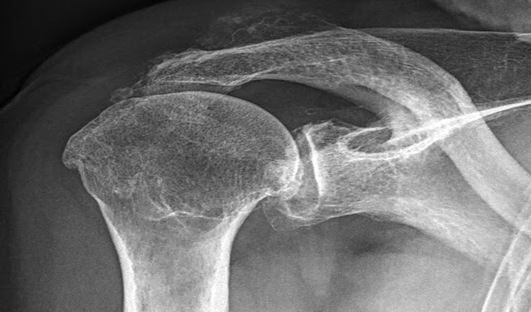

Le diagnostic de la luxation d’épaule est établi par de simples radiographies standards de face et de profil. Cette radiographie retrouve un pincement articulaire, c'est-à-dire une diminution de la distance entre les 2 surfaces articulaires, témoignant de la disparition du cartilage. Une fois le diagnostic fait, votre chirurgien demandera en plus la réalsation d’un scanner afin d’analyse de manière tri-dimensionnelle votre structure osseuse afin de planifier au mieux la prothèse. Il existe 2 grands types d’omarthrose :

C’est la forme “standard” d’arthrose de l’épaule. Le cartilage de la glène de l’omoplate ainsi que celui de la tête humérale sont atteints et amincis, le contact se fait “os contre os”. Les tendons de la coiffe des rotateurs sont intacts (une IRM peut parfois être utile pour analyser leur état). Cette arthrose survient généralement avant 60 ans. Les radiographies retrouvent une tête humérale centrée qui reste bien en face de la glène de l’omoplate

La radiographie retrouve une tête humérale ascensionnée par rapport à la glène de l’omoplate.